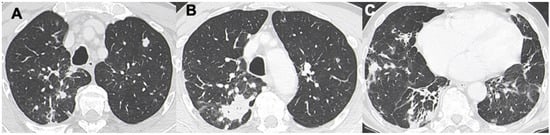

3.3. Ground-Glass Opacities

- Deng, W.; Wan, Y.; Yu, J.Q. Pulmonary MALT Lymphoma has variable features on CT. Sci. Rep. 2019, 9, 8657. [Google Scholar] [CrossRef]

- King, L.J.; Padley, S.P.; Wotherspoon, A.C.; Nicholson, A.G. Pulmonary MALT lymphoma: Imaging findings in 24 cases. Eur. Radiol. 2000, 10, 1932–1938. [Google Scholar] [CrossRef]

- Borie, R.; Wislez, M.; Antoine, M.; Copie-Bergman, C.; Thieblemont, C.; Cadranel, J. Pulmonary mucosa-associated lymphoid tissue lymphoma revisited. Eur. Respir. J 2016, 47, 1244–1260. [Google Scholar] [CrossRef] [PubMed]

- Wislez, M.; Cadranel, J.; Antoine, M.; Milleron, B.; Bazot, M.; Mayaud, C.; Carette, M.F. Lymphoma of pulmonary mucosa- associated lymphoid tissue: CT scan findings and patholo- gical correlations. Eur. Respir. J. 1999, 14, 423–429. [Google Scholar] [CrossRef] [PubMed]

- Chen, Y.; Chen, A.; Jiang, H.; Zhang, Y.; Zhu, L.; Xia, C.; Yu, H. HRCT in primary pulmonary lymphoma: Can CT imaging phenotypes differentiate histological subtypes between mucosa-associated lymphoid tissue (MALT) lymphoma and non-MALT lymphoma? J. Thorac. Dis. 2018, 10, 6040–6049. [Google Scholar] [CrossRef]

- McCulloch, G.L.; Sinnatamby, R.; Stewart, S.; Goddard, M.; Flower, C.D. High-resolution computed tomographic appearance of MALToma of the lung. Eur. Radiol. 1998, 8, 1669–1673. [Google Scholar] [CrossRef] [PubMed]